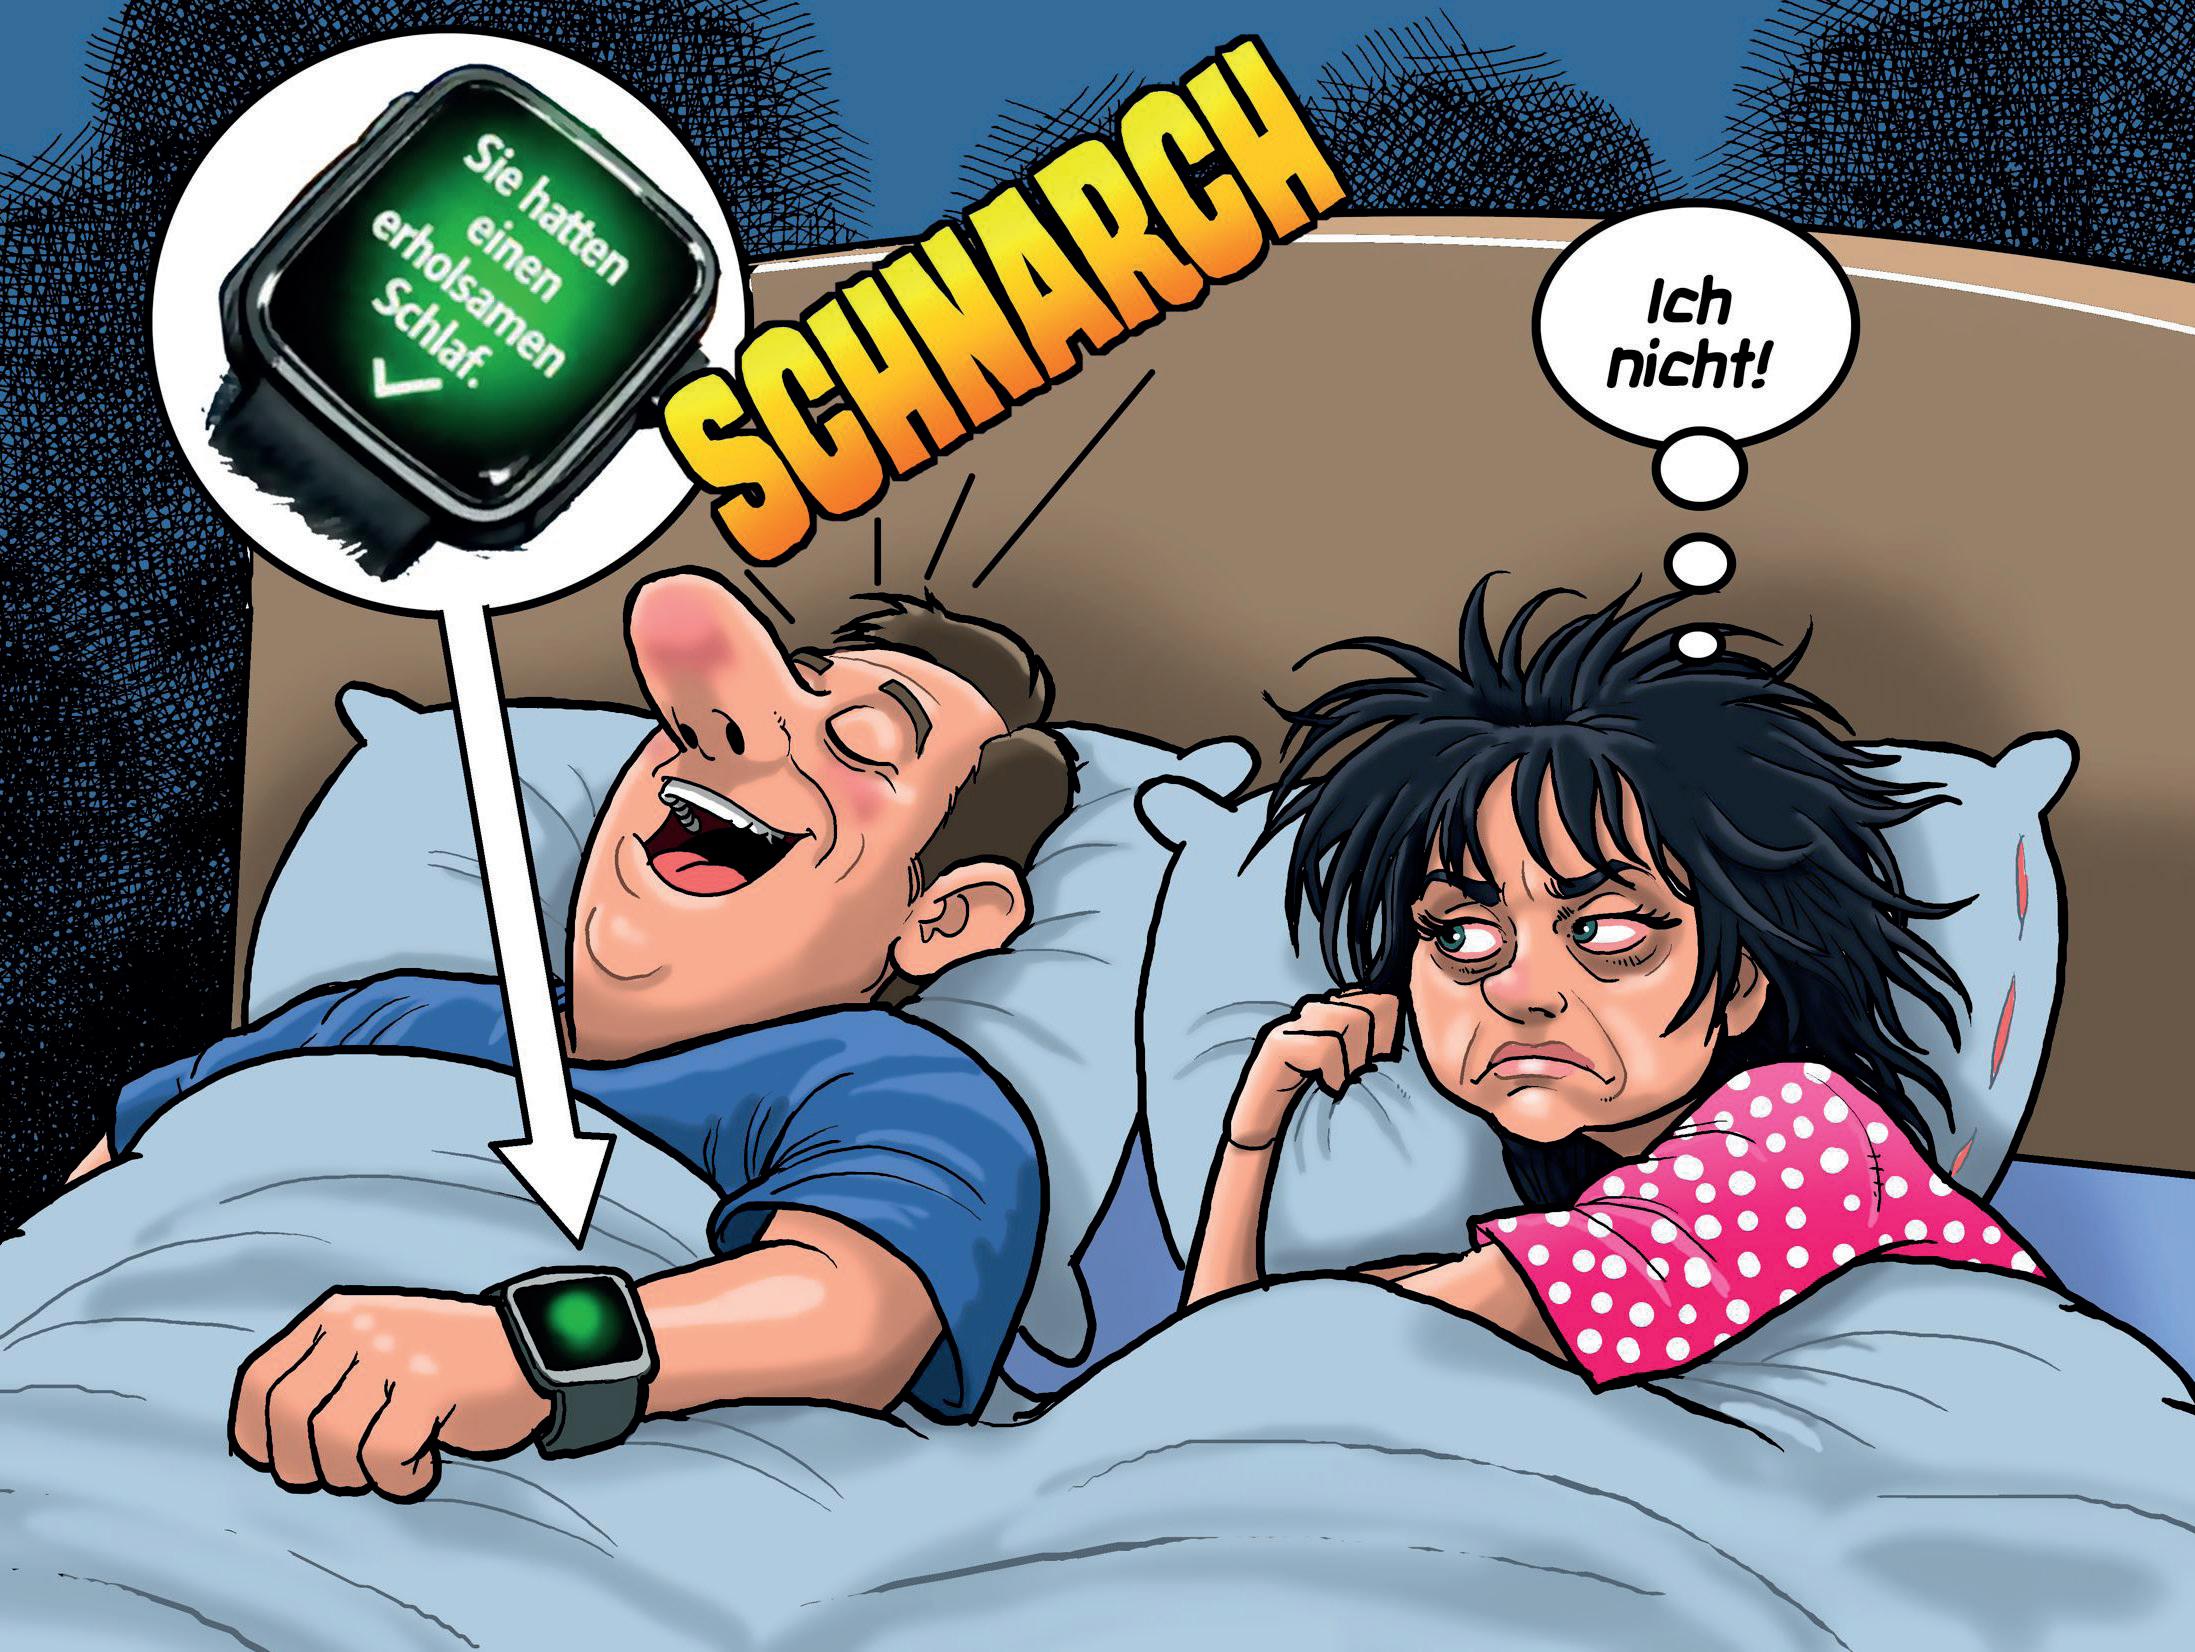

Ein neues KI-Modell kann mithilfe von Schlafdaten über 130 verschiedene Krankheiten erkennen – darunter Parkinson, Demenz und Herz-Kreislauf-Störungen. Forscher trainierten die KI mit umfangreichen Gesundheits- und Schlafmesswerten, um subtile Muster zu identifi zieren, die für menschliche Ärzte oft unsichtbar bleiben. Erste Tests zeigen: Die Genauigkeit bei bestimmten Diagnosen ist vielversprechend. Solche Systeme könnten künftig als ergänzende Hilfsmittel in der Frühdiagnose dienen und Ärzte bei der Analyse großer Datenmengen unterstützen. Vor einer breiten Anwendung stehen jedoch weitere Studien und ethische Abwägungen zum Datenschutz und zur Zuverlässigkeit.